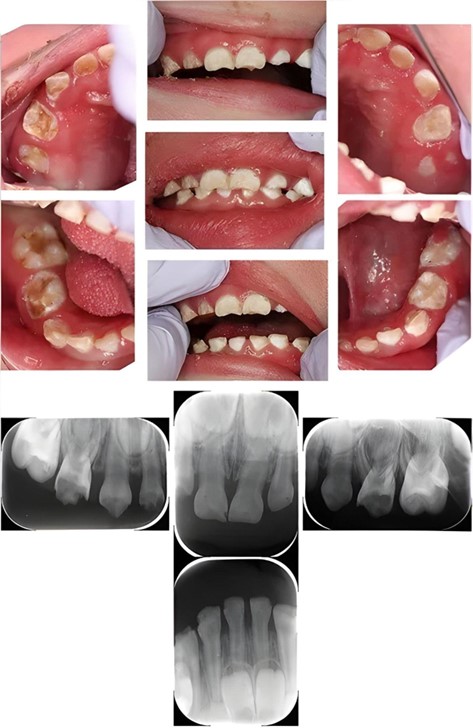

L’ittiosi congenita si manifesta con una disfunzione della barriera cutanea dovuta a mutazioni genetiche che alterano il metabolismo lipidico e la differenziazione epidermica. Tra le caratteristiche cliniche vi sono alterazioni dello smalto, ipoplasia dentale e rischio elevato di carie, come evidenziato nel caso analizzato. Questo quadro si complica ulteriormente nei pazienti pediatrici, che possono presentare anche disabilità intellettive o motorie, come nel paziente descritto.

A causa della giovane età, del comportamento non collaborativo e delle condizioni sistemiche, il paziente ha richiesto un trattamento odontoiatrico sotto anestesia generale. L’approccio è stato suddiviso in tre sessioni per minimizzare i rischi, in particolare quelli legati all’ipertermia, una complicazione comune nei pazienti con ittiosi congenita. Il trattamento ha incluso:

- terapie conservative: pulpectomia e restauri con corone prefabbricate.

- Gestione delle complicanze cutanee: adattamenti nel protocollo, come l’uso di fluoruri neutri per evitare irritazioni cutanee.